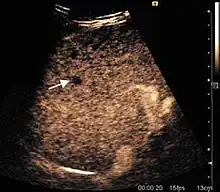

HCC appearance on 2D ultrasound is that of a solid tumor, with imprecise delineation, with heterogeneous structure, uni- or multilocular (encephaloid form). An "infiltrative" type is also described which is difficult to discriminate from liver nodular reconstruction in cirrhosis. Typically HCC invades liver vessels, primarily the portal veins but also the hepatic veins . Doppler examination detects a high speed arterial flow and low impedance index (correlated with described changes in tumor angiogenesis). The spatial distribution of the vessels is irregular, disordered. CEUS examination shows hyperenhancement of the lesion during the arterial phase. During the portal venous phase there is a specific "wash out" of ultrasound contrast agent (UCA) and the tumor appears hypoechoic during the late phase. Poorly differentiated tumors may have a stronger wash out leading to an isoechoic appearance to the liver parenchyma during portal venous phase. This appearance was found in approx. 30% of cases. The described changes have diagnostic value in liver nodules larger than 2 cm.

Ultrasound is useful in HCC detection, stadialization and assessing therapeutic efficacy. In terms of staging related to therapy effectiveness, the Barcelona classification is used which identifies five HCC stages. Curative therapy is indicated in early stages, which include very early stage (single nodule <2 cm), curable by surgical resection (survival 50-70% five years after surgical resection) and early stage (single nodule of 2–5 cm, or up to 3 nodules <3 cm) which can be treated by radiofrequency ablation (RFA) and liver transplantation. Intermediate stage (polinodular, without portal invasion) and advanced stage (N1, M1, with portal invasion) undergo palliative therapies (TACE and sorafenib systemic therapy) and in the end stage only symptomatic therapy applies.